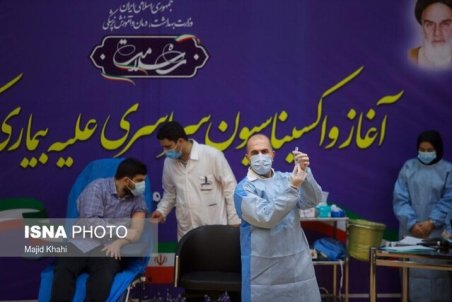

واکسیناسیون کرونا در اصفهان آغاز شد

مسئول بیماری های واگیر مرکز بهداشت اصفهان از آغاز واکسیناسیون کرونا در اصفهان همزمان با سراسر کشور خبر داد و گفت: ظهر امروز برای اولین بار، واکسن کرونا به پرسنل بخش آی سی یو بیمارستان عیسی بن مریم تزریق شد.